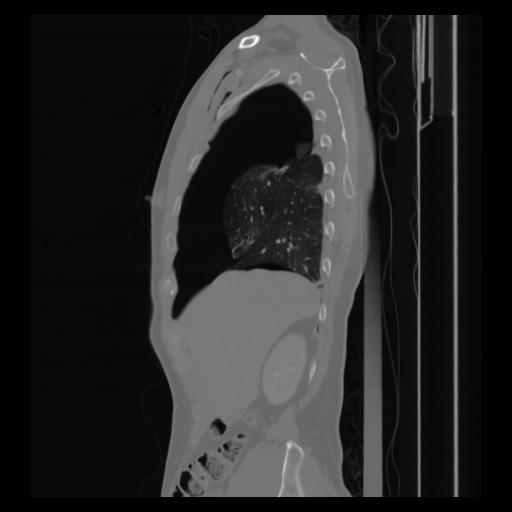

30 CUERPO,CE,Sagittal,3.000,CUERPO,Sagittal,